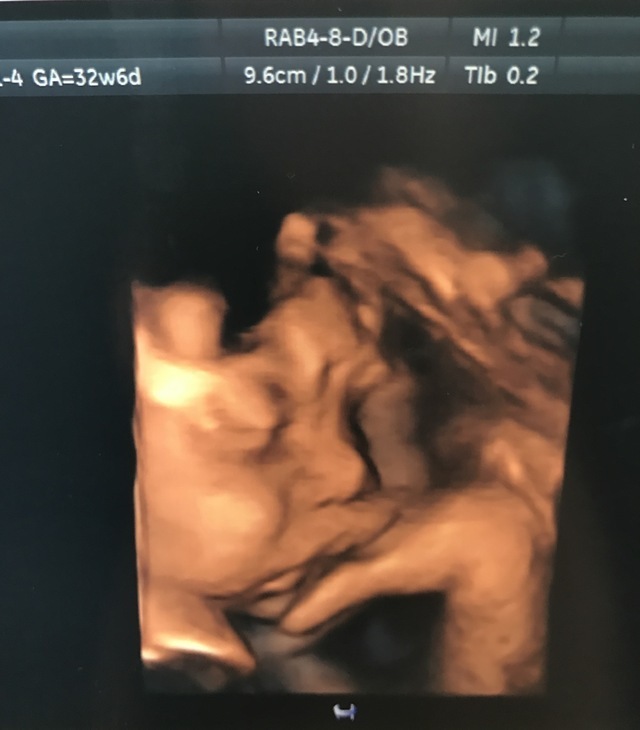

32週6日(32w6d・男の子)|サト さん(36歳)

エコー写真撮影時のエピソード:

エコー写真を親、兄弟にも見せています。最近でもエコー写真を貰える病院と貰えない病院があり、うちの家族ではとても珍しい物のようで、みんなで鼻が高いね、口元がかわいいね、と生まれて来る子どものことを話題にして楽しみに待っています。